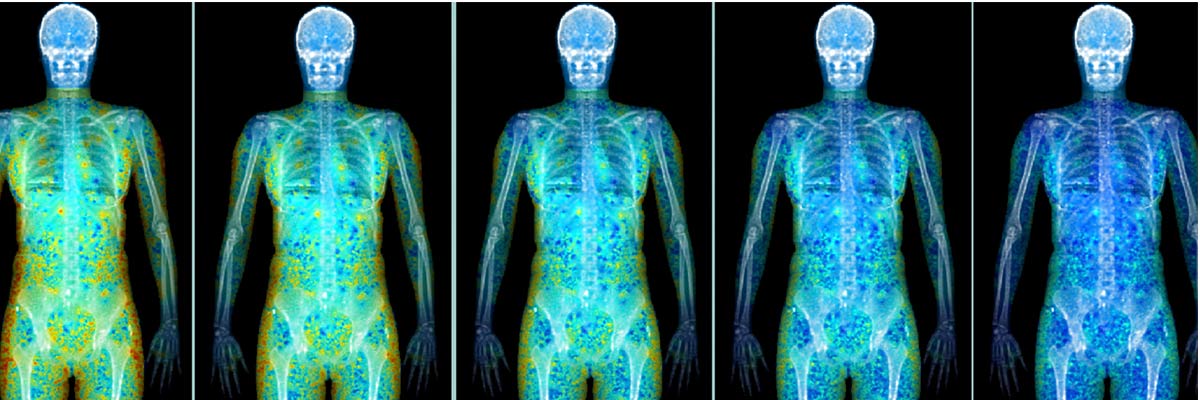

PETCT New

DRCTC is proud to have a mobile PET/CT scanner. This system boasts a wide variety of revolutionary advancements, including being the only Open Gantry Design PET/CT in the marketplace. The system produces the fastest total body imaging time of any PET/CT currently available and the multi-slice CT, allows for highly accurate and precise anatomical mapping.

PET imaging measures the body's metabolic activity. A patient receiving a PET scan is injected with a radioactive isotope which is in the form of glucose. Glucose is metabolized by all living cells in the body. The PET scan images the metabolic activity in the body. In the case of cancer, the cells function in a hyper metabolic state and this is seen on the PET scan.

Therefore PET scanning has become the gold standard in staging and restaging cancers. In cardiovascular and neurological diseases, the PET scan shows areas of increased, diminished or absent metabolic activity, therefore pinpointing abnormalities.

The advantage of PET/CT is that it is a hybrid imaging device, combining the best of seperate technologies. PET is a nuclear medicine imaging device that allows for very sensitive imaging of metabolic and functional processes. CT scanning is very strong in anatomical location. So by combining the units in to one single imaging device, you get the benefits of both technologies. When a patient has a PET/CT scan, the PET will identify areas of altered metabolism which indicate a disease state, and the PET images are fused with the CT images which are taken at the same time, allowing for the precise anatomical location of were the abnormal areas are seen on the PET scan. This gives the physician powerful diagnostic information,and allows the physician to plan the proper and most effective course of treatment.